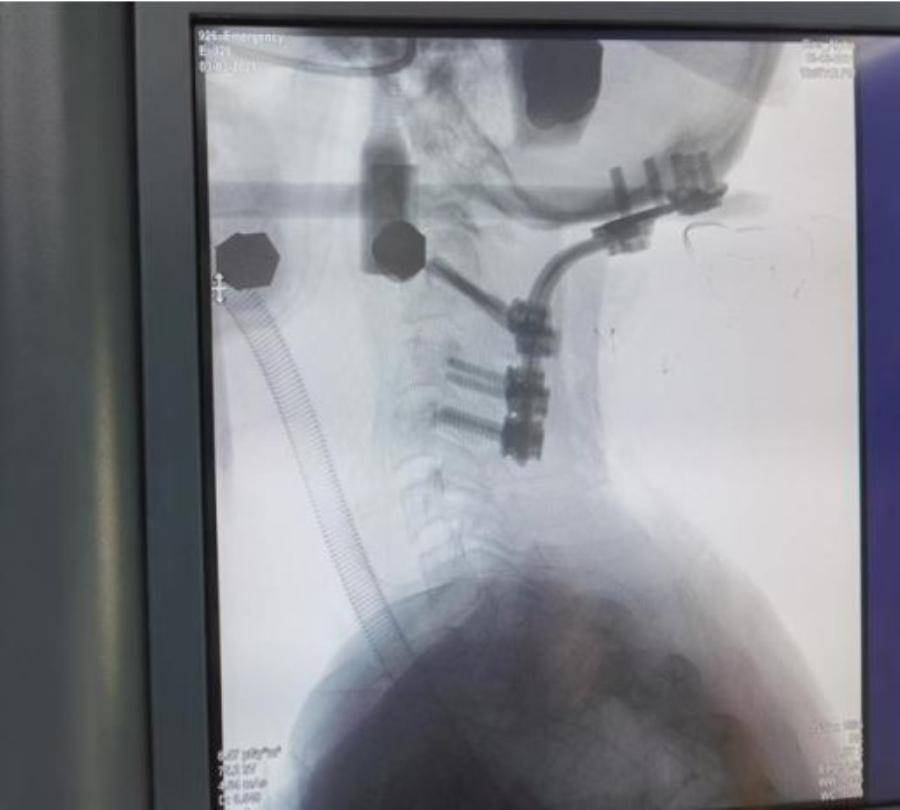

3月3日清晨,手术麻醉科按计划迎来了这位患者,麻醉科团队为患者进行麻醉前的精心准备,并备好了各种抢救药品,完善抢救预案。在可视化技术的辅助下,静脉给药,面罩给氧,平稳、准确、迅速地完成气管插管,为患者顺利地完成了全身麻醉。在颈椎外科、微创脊柱外科及麻醉科多名专家的团结协作和默契配合下,手术历时4小时顺利完成。术后患者自觉僵硬麻木缓解,肌力进步。目前患者生命体征平稳,正在接受进一步恢复治疗中。

术中照片

术毕颈椎X光片